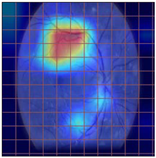

| Original Image | VGG16 | ResNet-18 | DenseNet-121 |

|---|---|---|---|

![]() | ![]() | ![]() | ![]() |

| (a) | |||

| (b) | |||

| (c) | |||

| (d) | |||